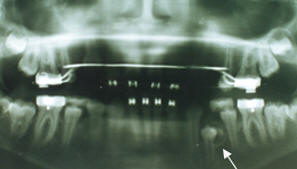

2 de abril, se

retiran aparatos en maxilar superior y al siguiente día se coloca un

retenedor tipo Hawley, el 22 de abril, retiro aparatos maxilar

inferior, se coloca un retenedor fijo entre caninos inferiores. Se

toman exámenes finales y en la radiografía panorámica se descubre la

presencia de otra pieza supernumeraria entre premolares inferiores

del lado derecho. Es importante recordar que el paciente ya fue

intervenido de otro supernumerario en el lado izquierdo que impidió

el normal desarrollo de la pieza 34, la que tuvo que ser fenestrada

y luego traccionada por medio de ortodoncia, lo que luego dio por

resultado recesión gingival en esa pieza. (Fig. 20).

|

|

Fig.

20.- En la que se puede observar la presencia de una

pieza supernumeraria en el sector inferior derecho,

además la presencia de los terceros molares, la pieza 48

por su inclinación mesial podría impedir o estar

obstaculizando la erupción de la pieza 47. Se solicita

la eliminación de la pieza supernumeraria y de los

terceros molares inferiores. |

2003

En el mes de enero

se controla al paciente quién ya se realizó la extracción de los

terceros molares inferiores. (Fig. # 24)

|

|

|

|

Fig. #

24.- Obsérvese que los terceros molares inferiores han

sido extraídos y también la pieza supernumeraria del

lado inferior derecho. Nótese la pérdida del tejido

dentario apical de la pieza 34, la cual se traccionó por

medio de un resorte de ortodoncia a fin de ayudarla en

su proceso eruptivo. Se puede ver la zona radiopaca

correspondiente al retenedor intercanino inferior. La

movilidad de la pieza dentaria desapareció y el premolar

aún con la pérdida dentaria apical, mantiene una

excelente fijesa. |